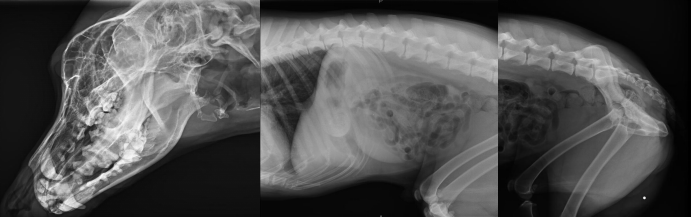

不管是人還是動物,有一項檢查是非常常見的,就是X光拍片檢查,X光檢查是傳統(tǒng)的影像學(xué)檢查手段,它是應(yīng)用較早、普遍,價格也相對便宜。主要用于一些疾病的初步檢查,便于發(fā)現(xiàn)較明顯病變的組織和結(jié)構(gòu),是疾病初篩優(yōu)選的檢查方式。那么,一般寵物拍X光片和人拍X光片有什么不同點,參數(shù)選擇一樣嗎?